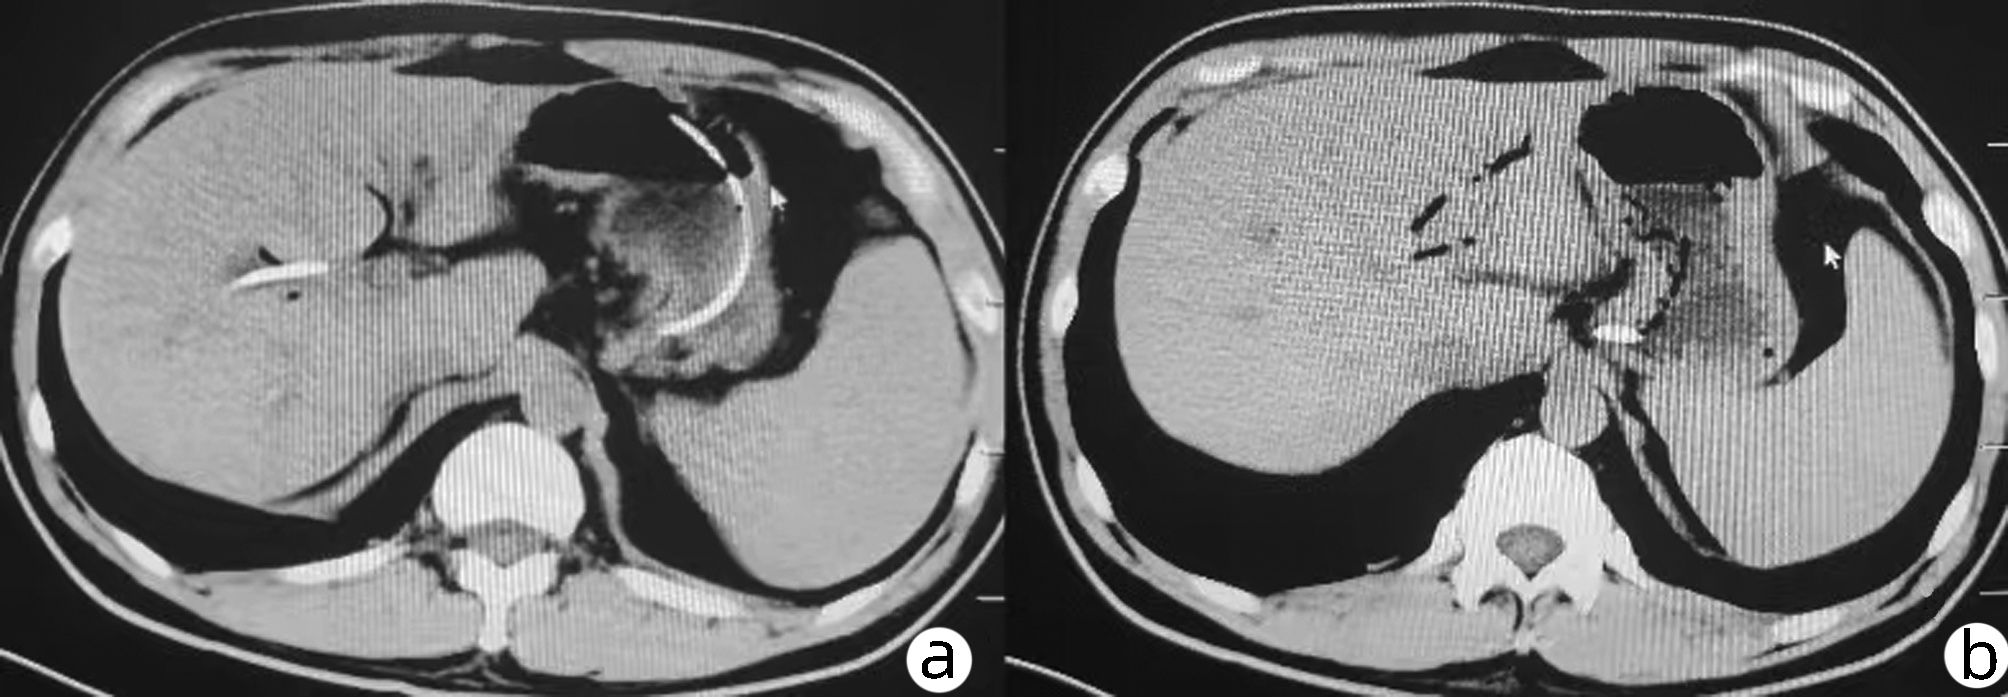

Short-term mortality and death causes after TACE in patients with primary liver cancer

Zhao LIU, Zhi LI, Kailun YANG, Siyin LI, Xiaoli ZHU, Caifang NI

2022, 38(11): 2510-2513. DOI: 10.3969/j.issn.1001-5256.2022.11.014

Abstract(1479) HTML (241) PDF (2070KB)(80)

Abstract:

Objective  To investigate the short-term mortality of transcatheter arterial chemoembolization (TACE) in patients with primary liver cancer, and explore the possible causes of death and countermeasures.  Methods  All patients who underwent TACE at the Department of Interventional Radiology, First Affiliated Hospital of Soochow University from January 2015 to December 2020 were studied, but those with metastatic liver cancer or receiving combined treatment were excluded. The clinical and imaging data of all patients were collected before and 30 days after TACE, and the clinical characteristics of the patients with short-term postoperative death were analyzed. Death within 30 days after TACE was defined as short-term death.  Results  A total of 1466 TACE in 741 patients with primary liver cancer were included. Ten patients (10/741, 1.35%) died within 30 days after TACE, with a mortality rate of 0.68% for all TACE. The mortality rate of d-TACE and c-TACE was 1.62% (3/185) and 0.55 % (7/1281), respectively. The mortality rates of patients at China Liver Cancer Staging Ⅰ, Ⅱ, and Ⅲ stages were 0.45% (2/448), 0.33% (2/599), and 1.43% (6/419), respectively. The mean diameter of the largest lesion in death cases was 10.1±0.8 cm. The possible causes of death were liver failure (4 cases), rupture bleeding (3 cases), myelotoxicity (1 case), pulmonary embolism (1 case), and heart failure (1 case).  Conclusion  The mortality rate after TACE in patients with primary liver cancer is low, with occasional short-term postoperative deaths. The death cases are characterized by a large tumor volume, and the most common causes of short-term death are liver failure and rupture bleeding.